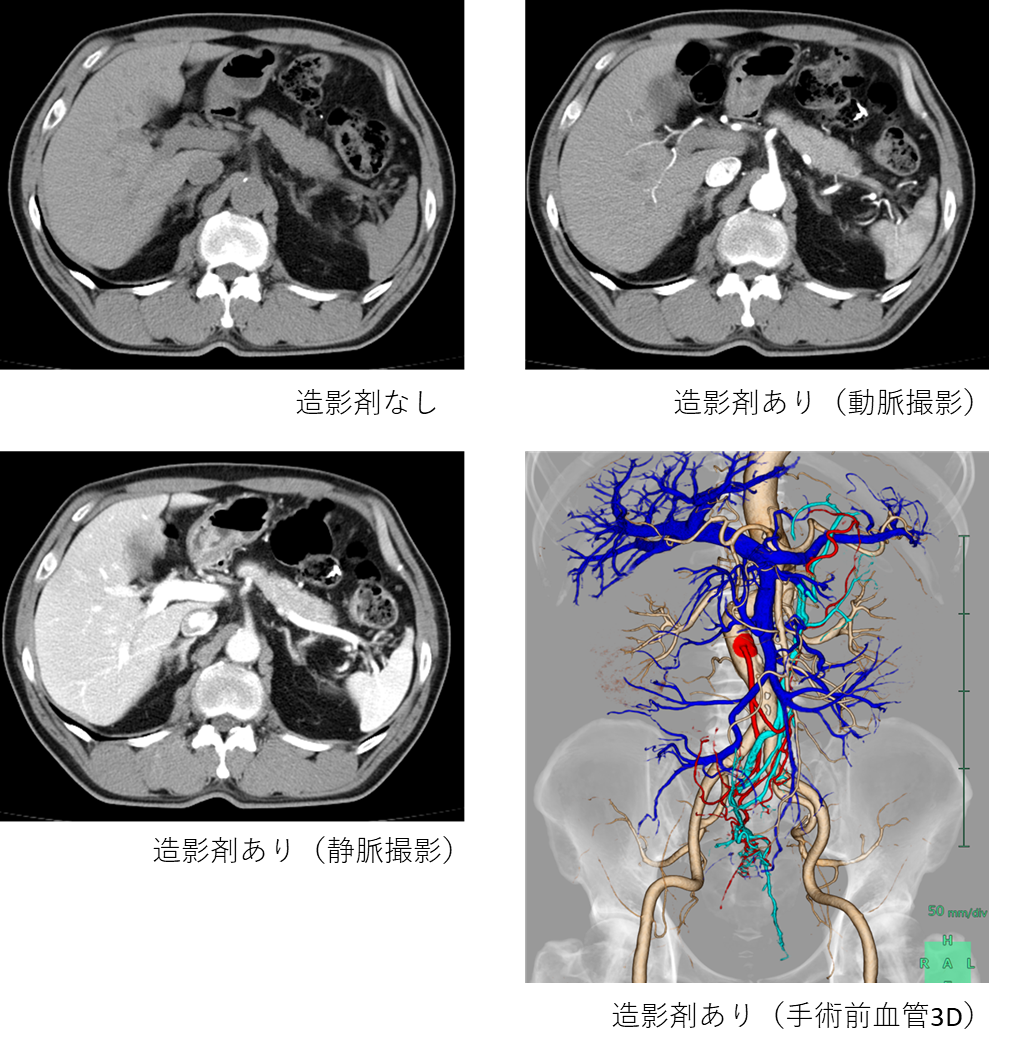

臓器や血管にコントラストをつけ、病気を見つけやすくするために使用するお薬です。造影剤を使用した画像データから腹部・心臓3D血管画像等の作成が可能となります。使用後、約1日で腎臓から尿中に排出されますが、まれに他のお薬と同様に副作用が起こることもあります。